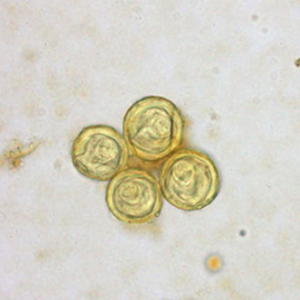

Les œufs de Bertiella sont ronds, transparents, à coque parfois épaisse, et mesurent 35 à 50 μm de diamètre. Ils renferment un embryon hexacanthe entouré par un appareil piriforme caractéristique. Bien que les œufs de Bertiella mucronata soient décrits comme plus petits que ceux de Bertiella studeri, il est impossible de les distinguer à l’examen coproscopique (Global Health, Division of Parasitic Disease and Malaria, 2019a).

L’identification des œufs de Bertiella ne pose pas de difficulté en général, l’embryon hexacanthe associé à l’appareil piriforme étant caractéristique (Furtado et al., 2012).